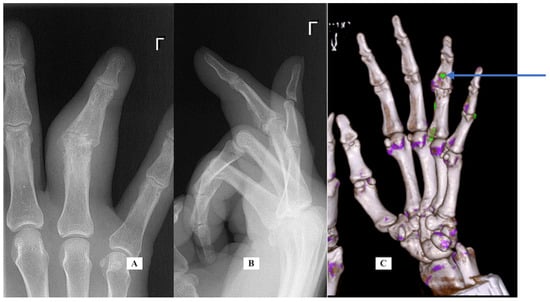

Case 1: A 22-year-old woman presented September 2018 with a 3-month history of right index finger swelling and stiffness localized to the PIP joint. There was no history of trauma and no other painful or inflamed joints. She had tried non-steroid anti-inflammatory drug (NSAID) medication, natural remedies, and occupational therapy, with no improvement. Her exam was notable for the swelling of the proximal phalanx and the PIP joint (Figure 1). She had mild PIP joint stiffness with flexion limited to 95 degrees (versus 105 degrees left F2). All labs for routine inflammatory screening (Table 1), X-rays and ultrasound were normal. She was sent for an MRI scan in October 2018 (Figure 1 center, post-contrast T1 fat suppressed) that demonstrated flexor tenosynovitis, joint synovitis and bone marrow edema. The report noted that “infection could not be ruled out”. She was taken to surgery (November 2018) with exploration under wide-awake local anesthesia no tourniquet (WALANT) for incisional biopsy of the thickened tenosynovium, both superficial and deep to the FDP tendon. The material was noted to be fibrotic and opaque in appearance. The material was sent for pathology, as well as cultures that included atypical mycobacterium. A specimen was sent for polymerase chain reaction (PCR—16S rDNA) testing. All the tests and cultures from surgery were negative, with pathology showing “nonspecific mild chronic inflammation” with a suggestion that “further clinical correlation is needed”. She was sent for a formal rheumatology evaluation and based on her presentation, psoriatic arthritis was suspected, and she was started on Sulfasalazine, which she took for 3 months without any improvement, so she elected to discontinue the medication. She adds that she had had no skin lesions in the past or on examination that would be consistent with psoriasis. Repeat labs for an underlying inflammatory disorder were carried out and again found to be normal. Repeat X-rays were carried out of her finger in January 2019, 6 months after the initial X-rays that showed soft tissue swelling, mild joint narrowing, and thick periosteal reaction involving the distal proximal and middle phalanges. Because there was still no improvement and no definitive diagnosis, a CT scan was performed. Her CT images from June 2021 (Figure 1, right) showed erosive changes at the PIP and DIP joints consistent with psoriatic arthritis. The CT findings were helpful in establishing a diagnosis and guiding future therapeutic options including starting biologics.

Figure 1. Case 1—clinical photograph of the enlarged PIP joint (A); MRI of the finger, sagittal view (B) demonstrating bone marrow edema at the base of P2; CT scan of the finger (C) demonstrating central erosions at the DIP joint (white arrow) and dorsal erosion at the PIP joint (blue arrow).